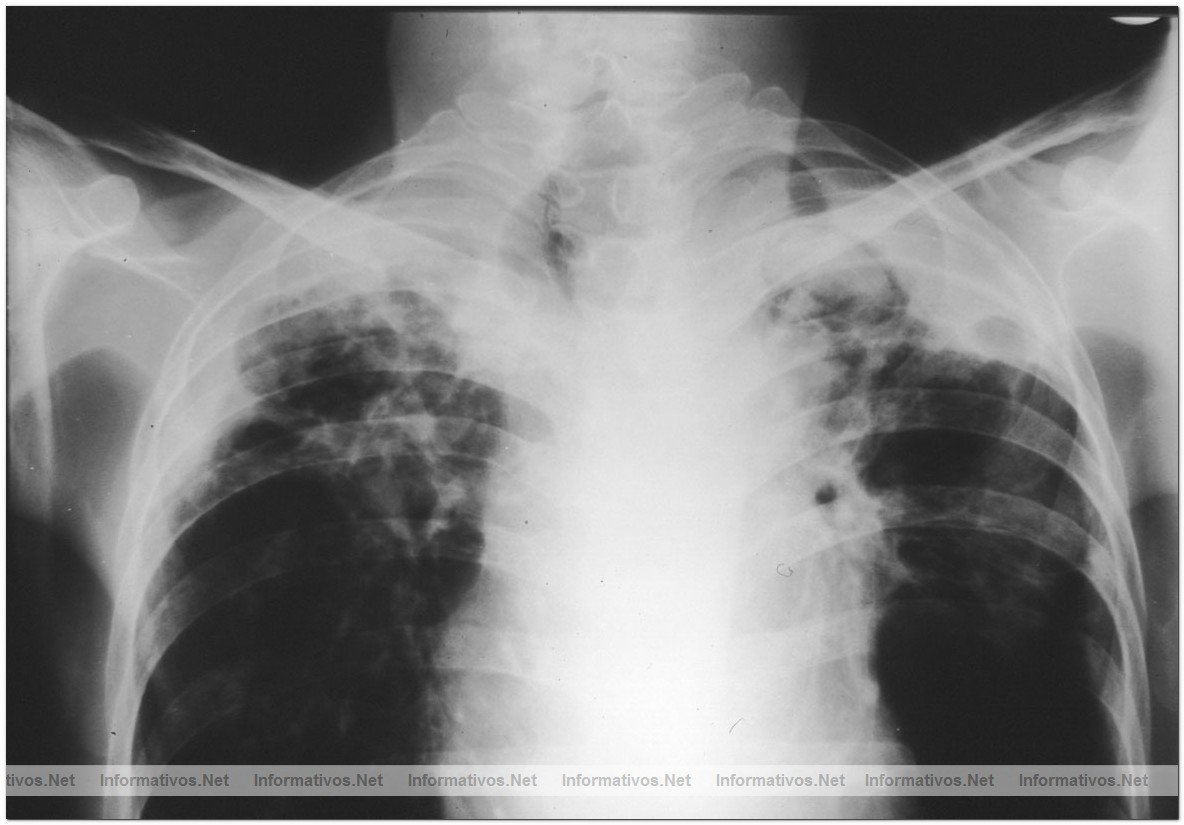

Barcelona forma parte de una investigación mundial contra la Tuberculosis, una enfermedad que afecta por lo general a los pulmones. La tuberculosis compromete otras partes del cuerpo, como el cerebro, los riñones o la columna vertebral. Si no se trata, la TB puede causar la muerte.